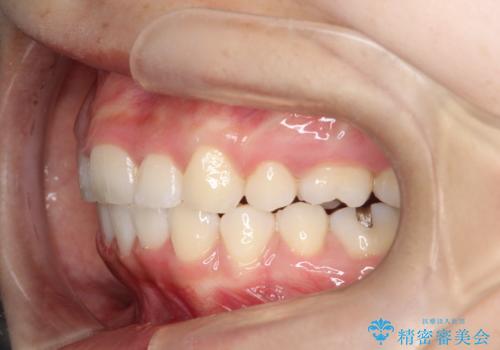

- 前歯のがたつきと出っ歯が気になるとのことで来院されました。

上顎の前から4番目の歯を両側合計2本抜歯して矯正することとなりました。

抜歯をして矯正をすることで、前歯を後方に移動させ、ガタガタを改善することができました。